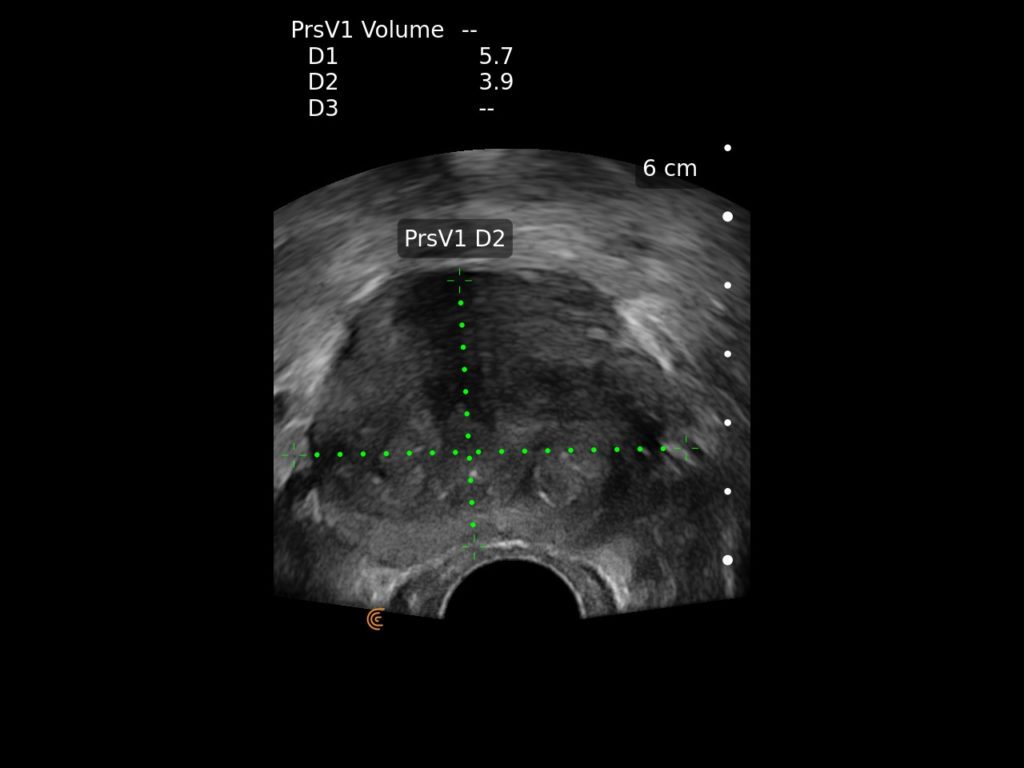

Clarius wireless ultrasound is the ideal system for your office or hospital practice with accurate, high-definition imaging readily available for diagnosis and therapy.